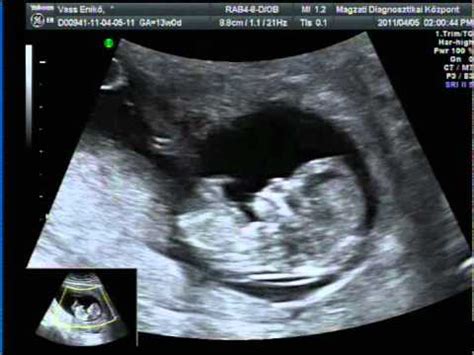

A 27. hétre a baba már jelentős méretet öltött. Majdnem 875 grammot nyom (akkora, mint egy fej karfiol) és nagyjából 36 centiméter hosszú. Már megvan a saját időbeosztása, hogy mikor alszik, és mikor van ébren, nyitogatja a szemeit és talán már az ujját is szopja. Mivel egyre több agyszövete fejlődik ki, az agya már nagyon aktív. Bár a tüdeje még nem fejlődött ki rendesen, már képes lenne a működésre - sok orvosi segítséggel - ha most születne meg a baba. Ha apró, ritmusos mozgásokat érzel, akkor ezt a baba csuklásának tudhatod be, ami mostantól gyakori lehet.

A 27 hetes magzat a hét végére már körülbelül 35 cm hosszú és a súlya is 1 kg körül van. A tüdő, a máj és az immunrendszer már működőképesnek számít, de még szüksége van a fennmaradó három hónapra ahhoz, hogy elérje érettségének maximális fokát. A magzat külseje nagyon hasonlít ahhoz, amilyen újszülött állapotában lesz, ugyan még sokkal kisebb és vékonyabb, és a bőr alatti zsírszövet hiánya miatt is még eléggé ráncos, de rohamosan fejlődik.

A 27. héten a magzat amellett, hogy meg tudja különböztetni a világosságot a sötétségtől, ki tudja nyitni és be tudja csukni a szemeit. Ezt folyamatosan gyakorolja a születéséig. A nyelvén kialakuló ízlelőbimbók segítségével már képes érzékelni a magzatvízből származó ízeket. A kismama táplálkozásától függ, hogy a magzat milyen ízekkel ismerkedik meg. Az elfogyasztott ételek íze bekerül a magzatvízbe. A látás és az ízlelés fejlődése szorosan összefügg az agy fejlődésével. Bár korábban még sima volt a felszíne, a 27. héten kialakulnak az első jellegzetes barázdák, amelyek a gondolkodás folyamatát és az érzékszervi észlelést teszik lehetővé. A magzat arányai tovább fejlődnek és egyre inkább hasonlítanak a szülés előtti állapotban jellemző arányokhoz. Míg a fej az elmúlt hetekben folyamatosan nőtt, ez a növekedés most lelassul és a test növekedéséhez idomul. A magzat még nem rendelkezik bőr alatti zsírszövettel, ezért bőre még mindig ráncos az egész testén. A zsírsejtek képződésével a ráncok fokozatosan eltűnnek és születéskor már alig láthatók. Innentől súlya egészen a születésig jelentős mértékben nő.

A táblázatot az ausztrál népesség átlagértékei alapján S. Campbell Westerway állította össze. Figyelem! A fenti táblázatokban szereplő értékek csupán támpontul szolgálnak, hogy körülbelül mikor, mekkora lehet a pocakodban növekedő baba, hogy ezáltal könnyebben lehessen elképzelni a picit!

| Paraméter | Érték (mm) |

|---|---|

| BPD (fejátmérő) | 68 (+/- 5,0) |

| HC (fej körfogat) | 250 (+/- 20) |

| AC (has körfogat) | 230 (+/- 25) |

| FL (combcsont hossz) | 50 (+/- 5,0) |

Fontos! A feltüntetett értékek hozzávetőlegesek, átlagértékek, a magzati kor, valamint az egyéni tényezők függvényében eltérőek lehetnek, ami nem jelenti azt, hogy bármilyen probléma lenne, ezzel kapcsolatban minden esetben az orvos a mérvadó. Az értékeket az ausztrál népesség átlag adatai alapján, S Campbell Westerway határozta meg.